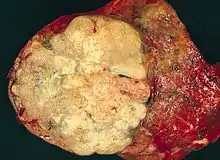

| A gross pathological specimen of a pulmonary adenocarcinoma, removed in a lobectomy. | |